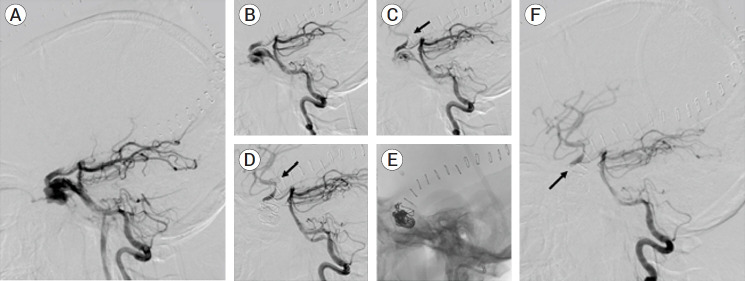

我们报告了一例 24 岁患者的病例,他在头部外伤后出现左侧颈内动脉外伤性闭塞。他接受了诊断性脑血管造影,发现左侧颈内动脉-海绵状静脉瘘(CCF)直接从后循环穿过后交通动脉逆行充盈。由于左侧颈内动脉(ICA)严重受损,无法进行ICA重建修复。患者采用后方逆行入路,通过线圈栓塞对CCF进行了解构修复。线圈被成功置入海绵窦并返回左侧 ICA,CCF 被完全治愈,治疗后的 CCF 远端恢复了脑灌注。我们回顾了CCF的类型、临床表现及其血管内治疗方法。文献中很少报道逆行进入直接CCF的方法,我们认为这种方法为经过适当选择的患者提供了一种可行的替代方案。

We report a case of a 24-year-old patient who presented after a head trauma with a traumatic occlusion of his left internal carotid artery. He underwent diagnostic cerebral angiogram and was found to have a direct left carotid-cavernous fistula (CCF) with retrograde filling from the posterior circulation across the posterior communicating artery. Because of the severe injury to the left internal carotid artery (ICA), reconstructive repair of the ICA was not possible. The patient underwent deconstructive repair of the CCF by coil embolization using a posterior retrograde approach. Coils were successfully placed in the cavernous sinus and back into the left ICA with complete cure of the CCF and restoration of cerebral perfusion distal to the treated CCF. We review the types of CCFs, their clinical presentation, and their endovascular treatments. Retrograde access of a direct CCF is rarely reported in the literature, and we believe this approach offers a viable alternative in appropriately selected patients.